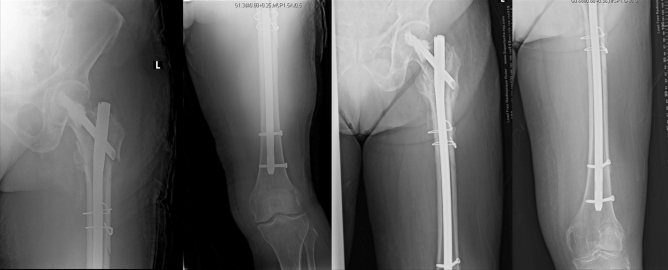

Fig. 4.

70/F who sustained an AO/OTA Type 31-A3 Fracture. Left: immediate post-op radiograph with a Neck-Shaft Angle (NSA) of 130°. Right: 2 months post-op showing fracture healing and NSA of 121°

Cut-out or cut-through of the head–neck element is considered one of the most devastating complications of cephalo-medullary fixation devices, requiring revision surgery (usually a total hip replacement) and exacting a greater physiological and financial burden on patients. Several studies have identified the quality of fracture reduction (i.e. NSA > 127° or within 5° of the contralateral hip) and the tip-apex distance (TAD) to be the most important factors that determine varus collapse of proximal femur fixation constructs. Varus collapse, along with head element placement in the postero-superior region of the head, in turn, increased the risk for cut-out [2, 16–21]. While most studies stipulate that the difference between fixation with a lag screw versus a helical blade is not as significant as anatomical reduction, proper implant positioning and TAD, constructs which feature a helical blade have been documented with considerably reduced cut-out rates (somewhere between 1.5 and 7% as compared to 2.9–14% for lag screws) and, as such, is the preferred cephalo-medullary fixation component, particularly in osteoporotic bone [1–5, 7, 16]. In our study, all patients were fixed with the helical blade, except for one—a young male patient with a bifocal femoral fracture who, save for delayed union of his diaphyseal fracture by a few weeks, went on to heal uneventfully. Additionally, two patients had varus collapse of more than 5 degrees, but neither patient progressed into cut-out/cut-through (Fig. 4).